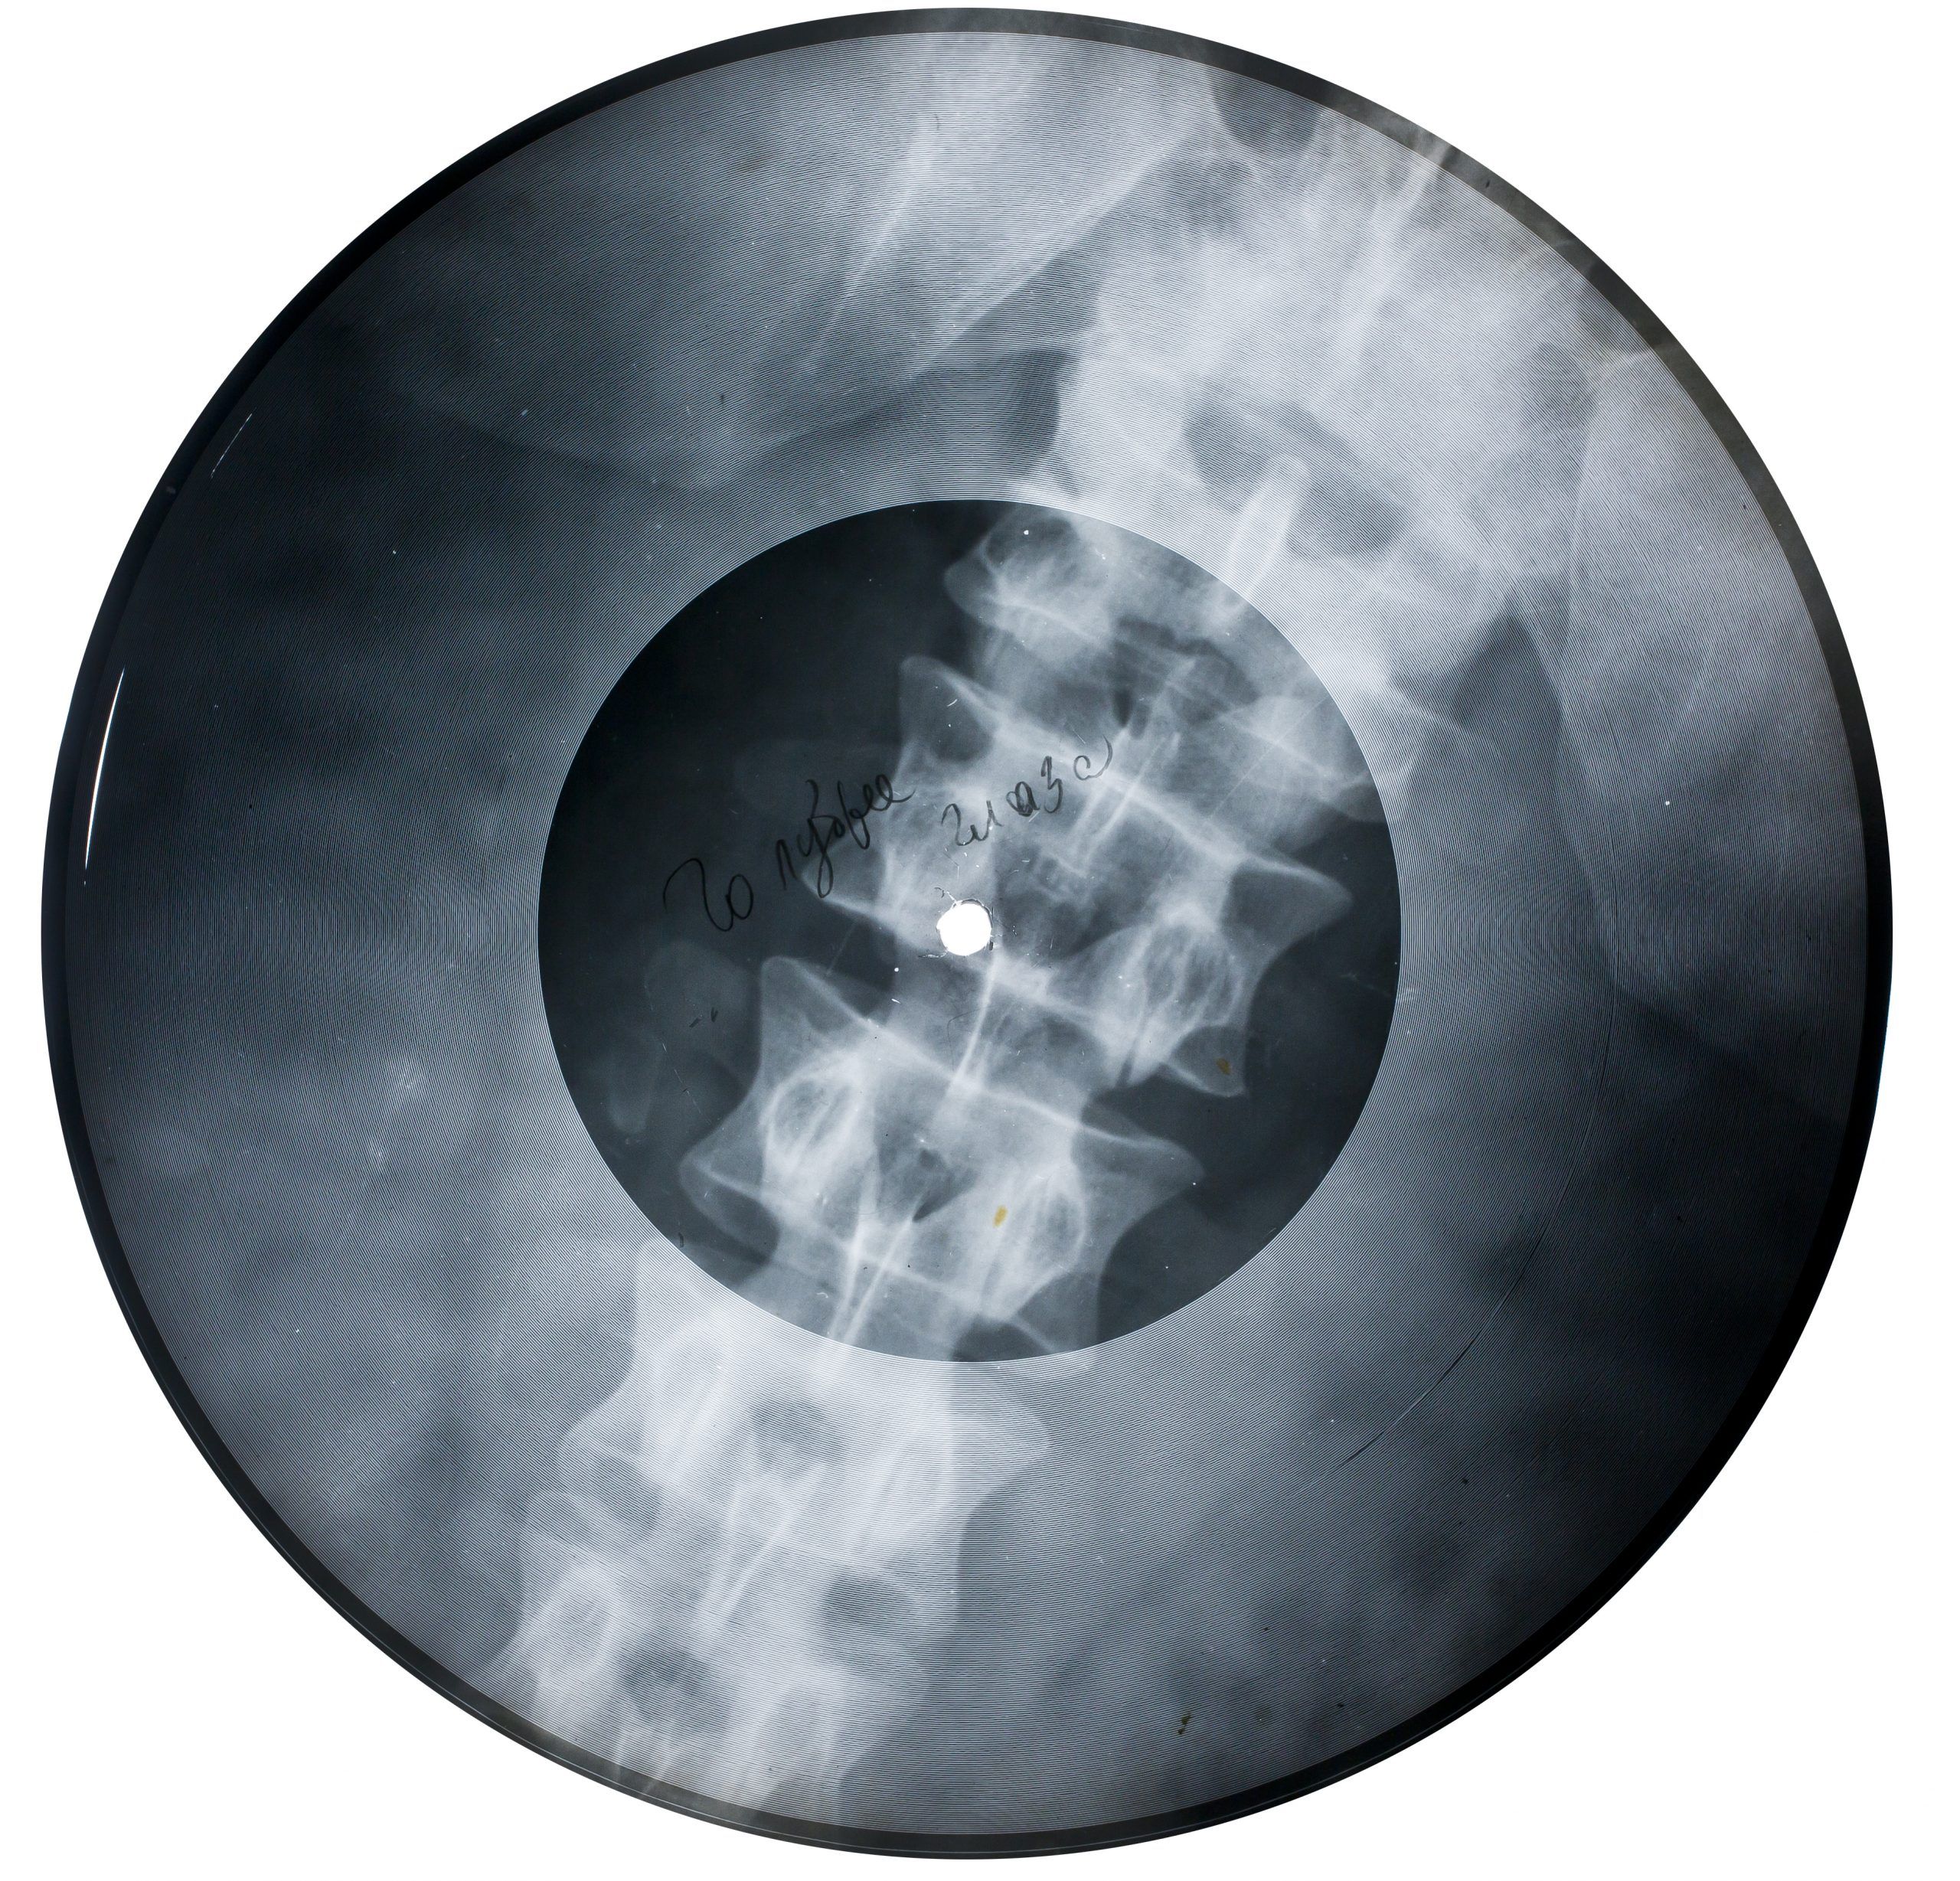

X-RAY MAGAZINE VOL1 number4 1995 洋書, X-RAY AUDIO: The “Bone Music” of the Soviet Union | 032c,

X-RAY AUDIO: The “Bone Music” of the Soviet Union | 032c, Hacker II: The Doomsday Papers | Magazines from the Past,

Hacker II: The Doomsday Papers | Magazines from the Past,![X Japan – Trance X – CD (Album), 2002 [r257430] | Discogs X Japan – Trance X – CD (Album), 2002 [r257430] | Discogs](https://i.discogs.com/P4deBAb7NpOoztOBLQG8HXU28A7ZAthOFufpYDELK-o/rs:fit/g:sm/q:90/h:600/w:588/czM6Ly9kaXNjb2dz/LWRhdGFiYXNlLWlt/YWdlcy9SLTI5ODE4/MTkyLTE3MDgwODk3/MDItODE5MS5qcGVn.jpeg) X Japan – Trance X – CD (Album), 2002 [r257430] | DiscogsX-RAY MAGAZINE VOL1 number4 1995です。世界200冊限定でそれぞれアーティストがテーマ別に作品を展開したアートブックです。Amazonでも400ドル以上の高値で取引されており、この価格はお買い得かと思います。破れなどございません。26年前の中古品につきご理解のある方宜しくお願い致します。お探しだった方是非。

X Japan – Trance X – CD (Album), 2002 [r257430] | DiscogsX-RAY MAGAZINE VOL1 number4 1995です。世界200冊限定でそれぞれアーティストがテーマ別に作品を展開したアートブックです。Amazonでも400ドル以上の高値で取引されており、この価格はお買い得かと思います。破れなどございません。26年前の中古品につきご理解のある方宜しくお願い致します。お探しだった方是非。